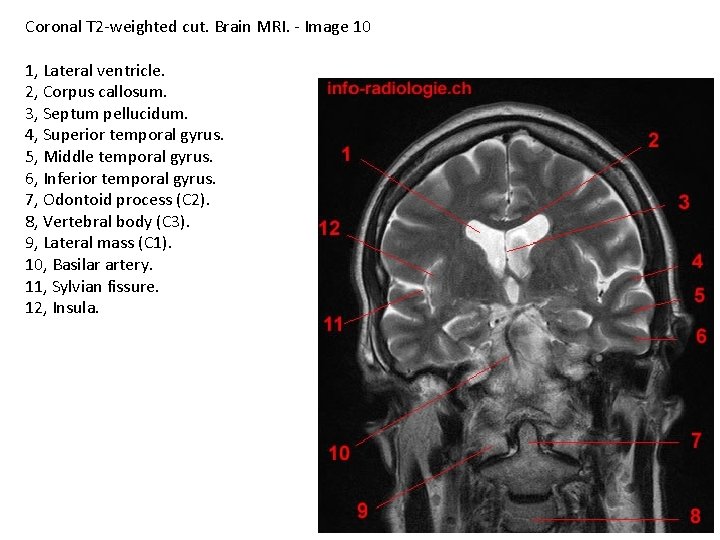

Coronal T 2 -weighted cut. Brain MRI. - Image 10 1, Lateral ventricle. 2, Corpus callosum. 3, Septum pellucidum. 4, Superior temporal gyrus. 5, Middle temporal gyrus. 6, Inferior temporal gyrus. 7, Odontoid process (C 2). 8, Vertebral body (C 3). 9, Lateral mass (C 1). 10, Basilar artery. 11, Sylvian fissure. 12, Insula.